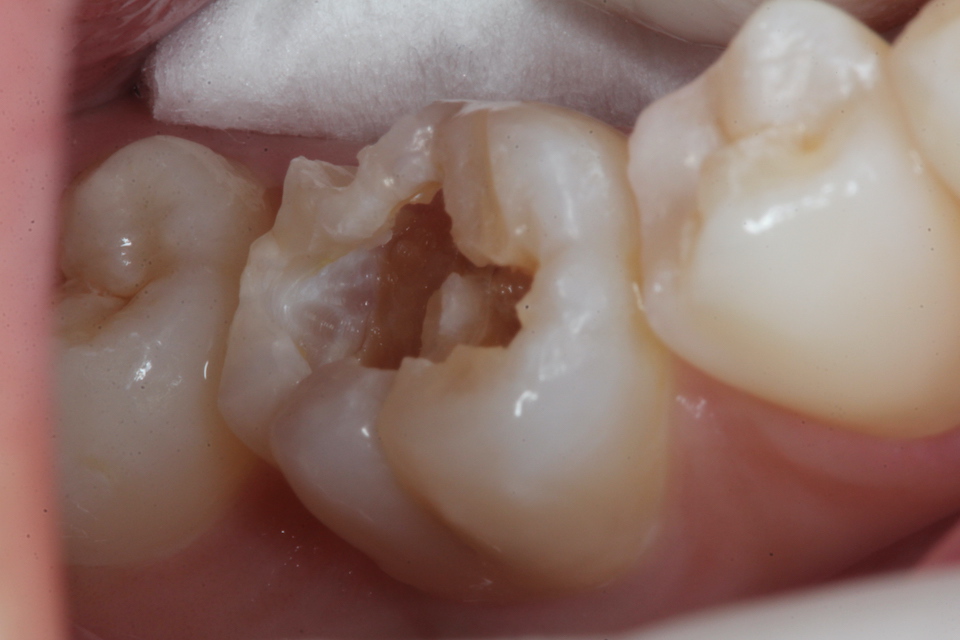

虫歯を除去していく過程

3MIX+α-TCP